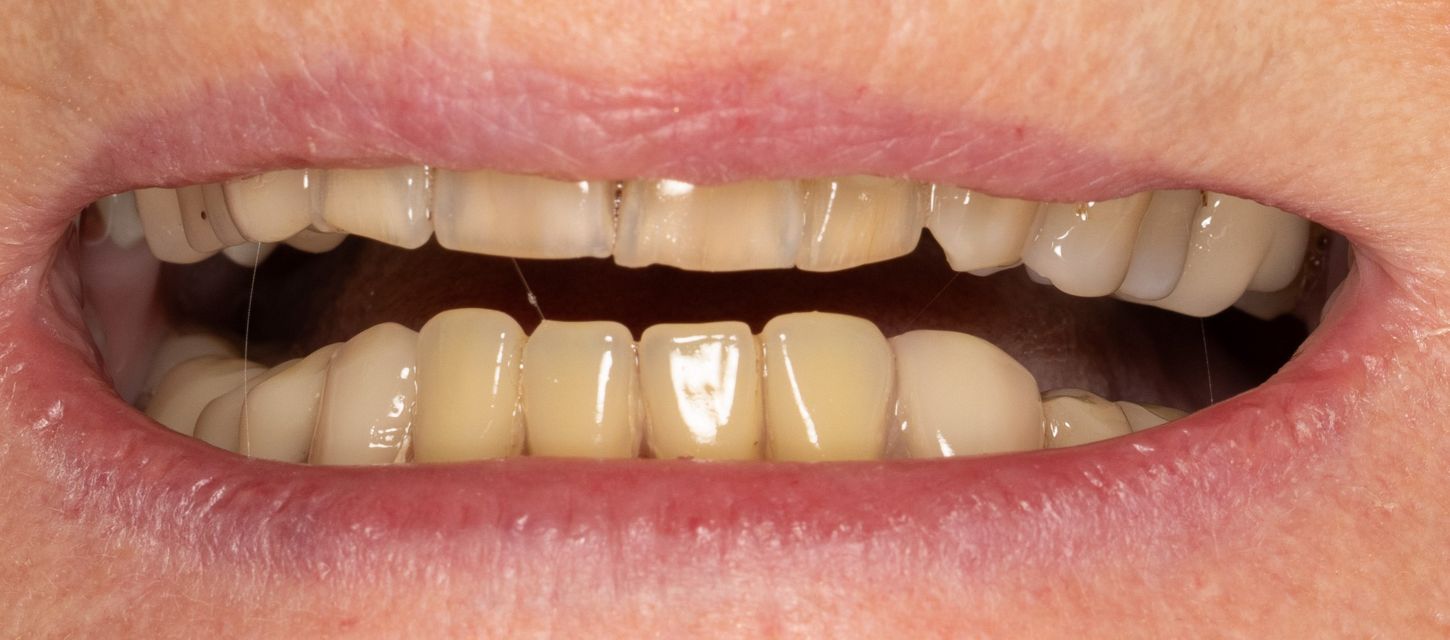

2. Intraoral examination.

2a. View of the mouth showing limited gingival exposure.

2b. Situation in the maxilla: the periodontal situation is stable.

2c. Situation in the mandible: thin alveolar crest and residual teeth 33 and 43.